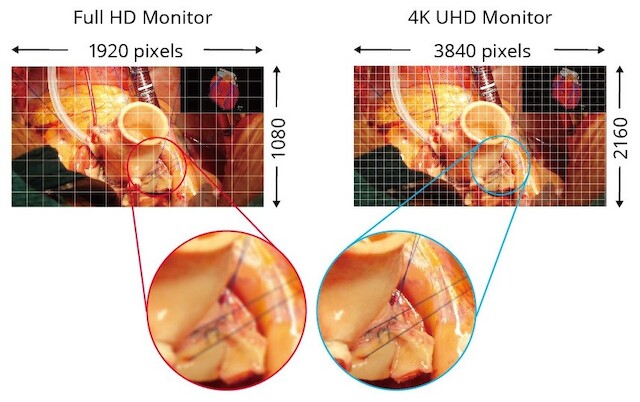

全世界的人均寿命都在不断延长,因此对病人温和的微创手术变得越来越重要。手术的成功在很大程度上取决于细致的成像流程,它能使外科医生尽可能准确地协调手眼动作。因此,除了高分辨率监视器外,3D 成像技术也进入了手术室。逼真的光学景深成像可实现更精确、更快速的干预。到目前为止,在手术室设备推车上灵活使用的 4K UHD 3D 技术仅限于尺寸较小的显示器,最大尺寸为 32 英寸,这只能显示图像的一小部分。而 55 英寸的较大对角线尺寸屏幕则只能永久安装在墙壁和天花板支架上。